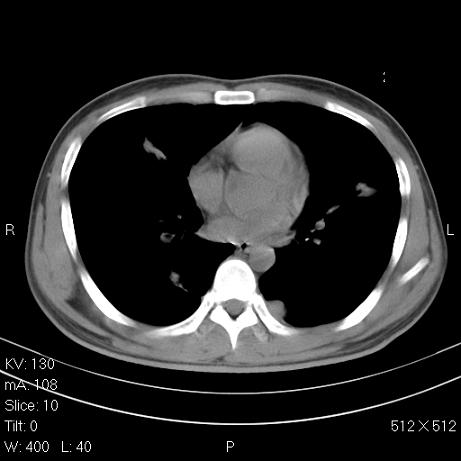

标题: CT7171B:补充治疗后2周复查

治疗后2周复查,请讨论

结合以前的ct片,还是考虑肺挫伤,吸收多了。

支持:创伤性湿肺。现肺挫裂伤(出血 积气)大部分吸收。建议继续治疗!

支持:创伤性湿肺、肺挫裂伤。现肺挫裂伤(出血、渗出、液气腔)大部分吸收。建议继续治疗!

经治疗后病灶明显吸收,考虑创伤性湿肺、肺挫裂伤

应该为多发性外伤性肺囊肿.